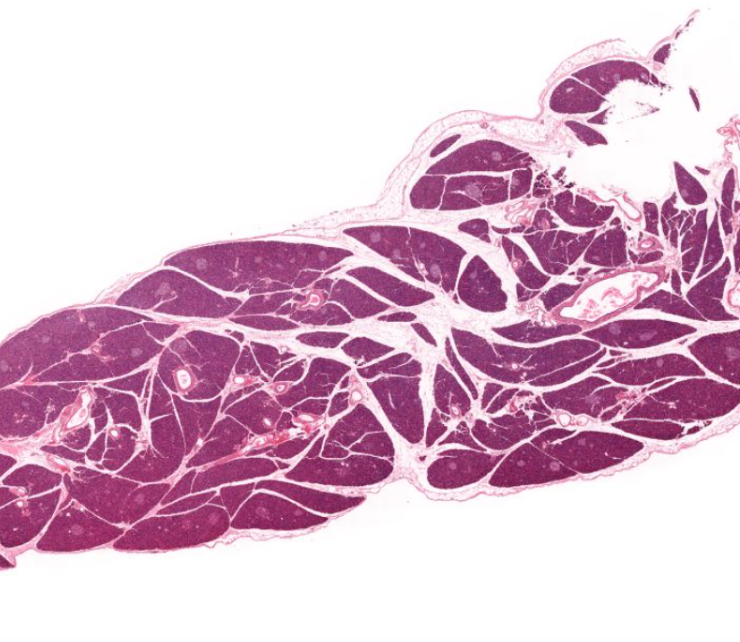

pancreas

looks like a shitty purple unicorn horn

exocrine secretes digestive enzymes

endocrine releases insulin and glucagon